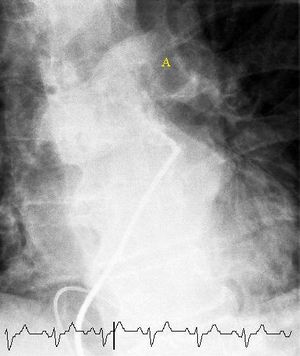

Selective pulmonary angiogram revealing clot (labeled A) causing a central obstruction in the left main pulmonary artery. ECG tracing shown at bottom.

أفضل تصوير شعاعي متاح لتشخيص الانصمام الرئوي هو تخطيط الأوعية الدموية في الرئة، ولكن نظرً لكون هذا الإجراء باضعاً (Invasive) وينطوي على بعض المضاعفات الجانبية فإن استخدامه يبقى محدوداً.